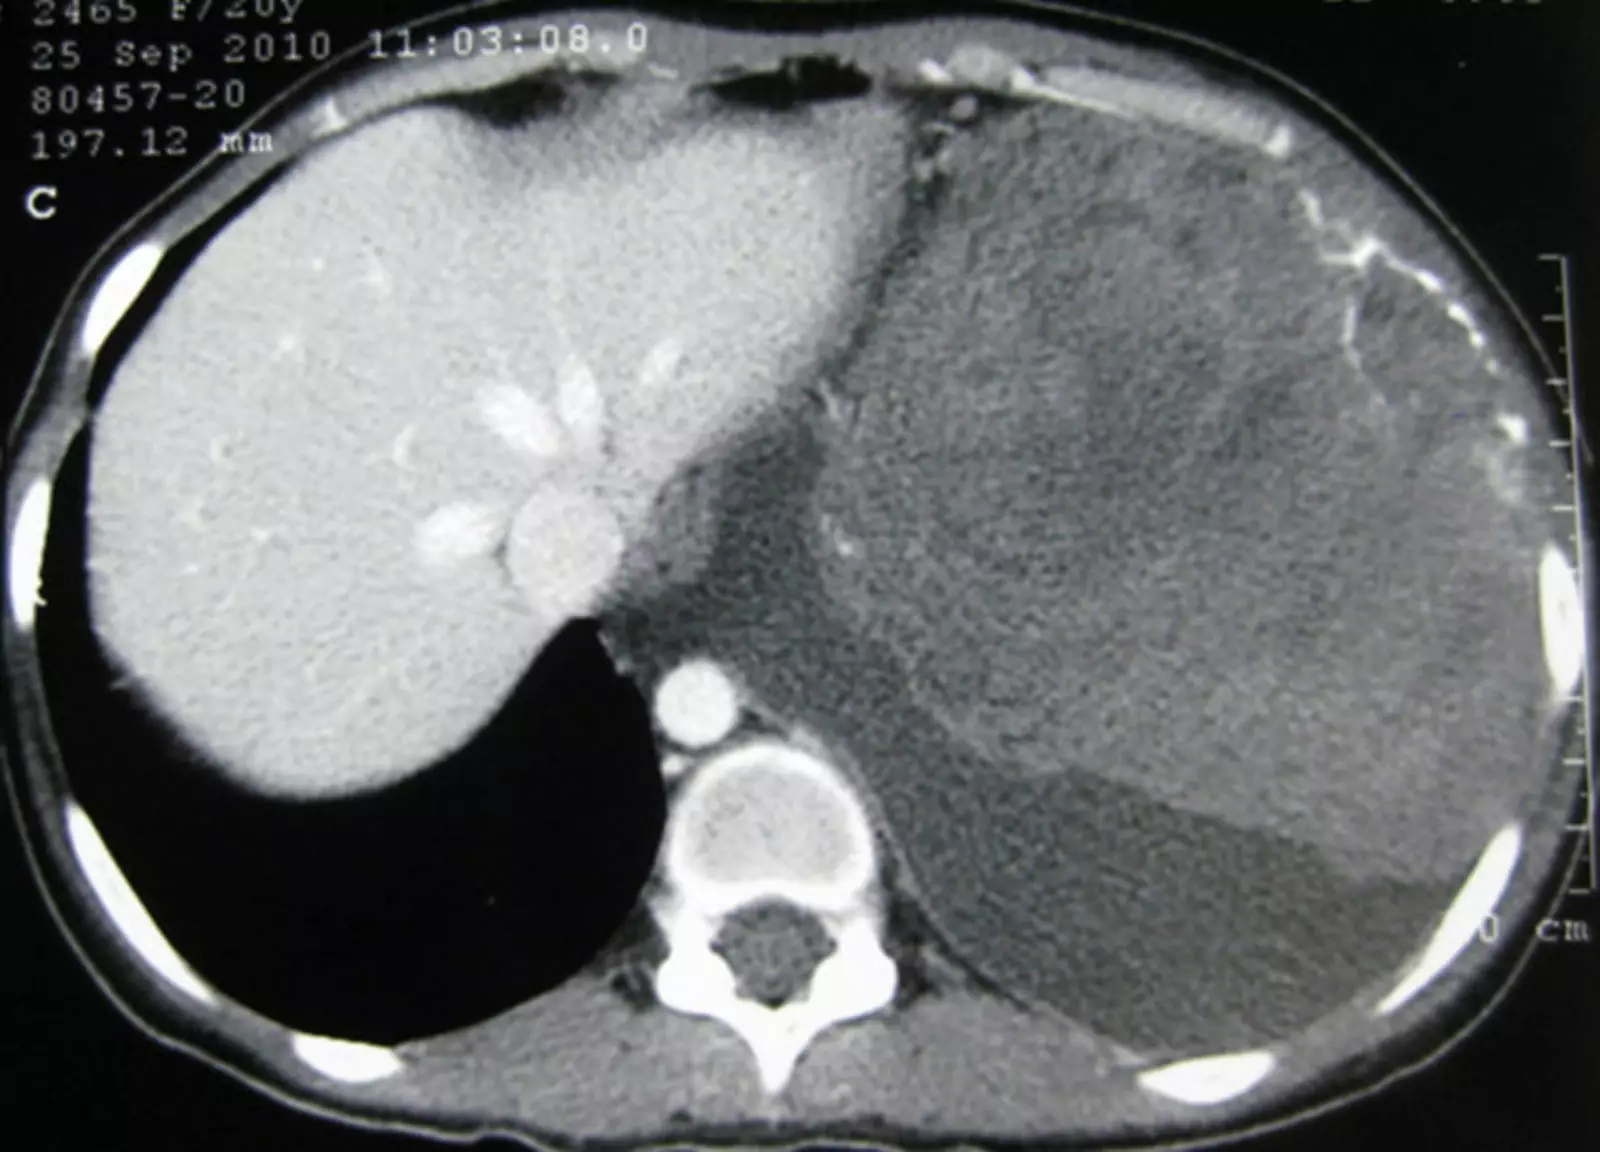

Нейробластома.